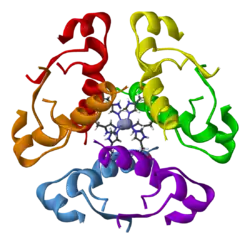

Insulin glargine

Insulin glargine is a long-acting modified form of medical insulin used in the management of type 1 and type 2 diabetes.[151] It is administered through subcutaneous injection. Its effects typically begin within an hour of injection.[151][152]

Common side effects include (hypoglycemia, issues at the injection site, itchiness, and weight gain.[151] NPH insulin is generally preferred over insulin glargine during pregnancy.[153] After injection, microcrystals gradually release insulin over a period of approximately 24 hours.[151] This insulin works by facilitating the absorption of glucose by body tissues and reducing glucose production by the liver.[154]

Insulin glargine was patented, although the patent expired in most countries in 2014. It was approved for medical use in the United States in 2000.[152] It is listed on the World Health Organization's List of Essential Medicines.[78] In 2022, it ranked as the 28th most commonly prescribed medication in the United States, with more than 18 million prescriptions.[28][155] In July 2021, the US Food and Drug Administration (FDA) approved an interchangeable biosimilar insulin product, Semglee (insulin glargine-yfgn), for the treatment of diabetes.[156] Unbranded versions of insulin glargine and insulin glargine-yfgn are sold by Sanofi[157] and Viatris.[158]